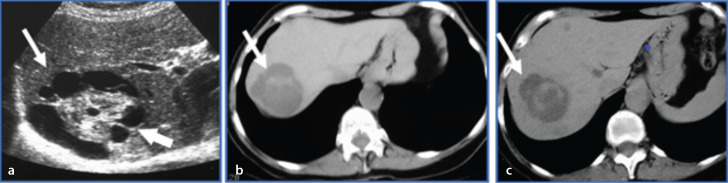

肝脏的非肿瘤样病变可能与肝肿瘤相似。在许多情况下,需要进行活组织检查以确认病理。不过,有几种肿瘤样病变可以得到正确诊断或前瞻性建议,从而使患者免于不必要的焦虑和花费。在这篇以图像为重点的综述中,我们介绍了八个此类实体的超声、计算机断层扫描、磁共振成像和正电子发射断层扫描特征。讨论了提示正确病理的线索,并描述了通常的临床环境。许多此类病变的治疗方法与真正的肿瘤不同,在介绍的许多病例中还讨论了当前的治疗方案。阅读完本文后,读者将对这些病变有更好的了解,并知道在哪些情况下应将其纳入鉴别诊断。

Non-neoplastic tumor-like conditions of the liver can appear similar to hepatic neoplasms. In many cases, a biopsy is required to confirm the pathology. However, several tumor-like conditions can be correctly diagnosed or suggested prospectively, thus saving patients from unnecessary anxiety and expense. In this image-focused review, we present the ultrasound, computed tomography, magnetic resonance imaging, and positron emission tomography scan features of eight such entities. Clues that indicate the correct pathology are discussed, and the usual clinical setting is described. Many of these lesions are treated differently from true neoplasms, and the current treatment plan is discussed in many of the cases presented. After reviewing this article, the reader will have a better understanding of these lesions and the situations in which they should be included in the differential diagnosis.